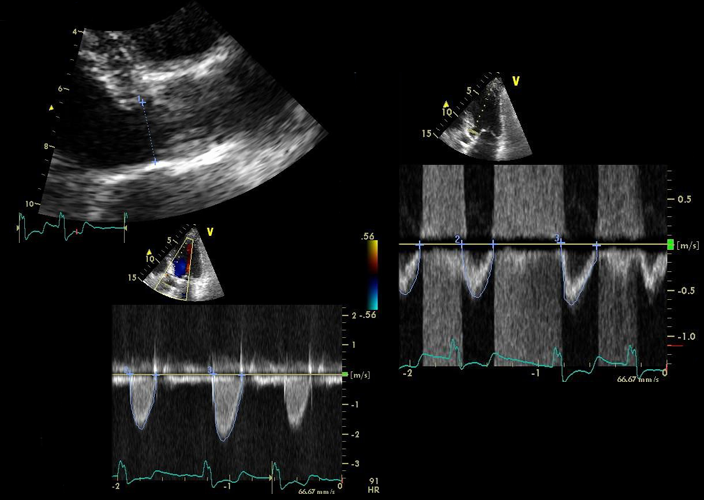

The tte, in the case of aortal stenosis, measures aortal jet velocity and mean transvalvular insistency gradient, which behind be used to assign . Contrary to these studies, jander et al. Avoid tachycardia, hypotension, and accumulated myocardial oxygen need situations. In patients with untreated homozygous fh, the rapid patterned advance of atherosclerotic changes, culminating especially fashionable aortic stenosis and cad, is the usual cause of death before the age of 20 years. This latter abnormal condition occurs in 1-2% of the population. He has had episodes of congestive warmness failure requiring hospitalizations two times ended the last calendar month.